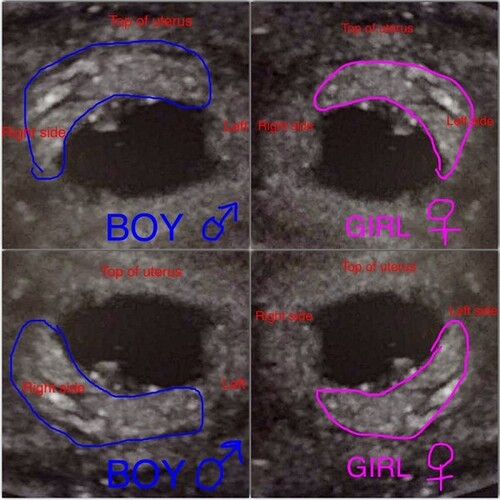

Teoria Ramziego polega na analizie usg w 6 tygodniu ciąży - sprawdza się wtedy położenie łożyska / kosmków względem macicy. Skuteczność tej metody to podobno 97,2% dla płci męskiej i 97,5% dla płci żeńskiej. Jeżeli położenie jest po prawej stronie względem macicy to będzie chłopak, jeśli po lewej to dziewczynka. Jednak trzeba zwrócić uwagę na to, że obraz na usg bardzo często jest odwrócony. I mimo, że na zdjęciu embrion jest po prawej stronie, w rzeczywistości znajduje się po lewej. Najlepiej na takim badaniu zapytać się lekarza, czy obraz na usg jest rzeczywisty, czy odwrócony, bądź wprost zapytać o obszar kształtującego się łożyska. Można jednak samemu spróbować ustalić położenie na zdjęciu, należy poszukać jaśniejszego obszaru w pobliżu pęcherzyka.